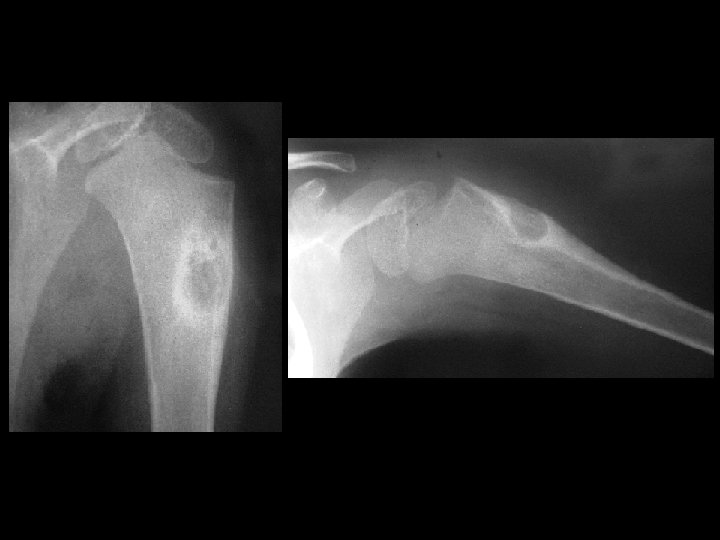

Osteoblastoma • • • 4. 4 m. Ci Tc-99 m MDP, i. v. focal intense activity in the proximal humeral metaphysis eccentric oval lytic lesion with periosteal reaction also occurs in the posterior elements of the spine and long bones histologically similar to osteoid osteoma ddx: – – giant cell tumor ABC non-ossifying fibroma osteosarcoma